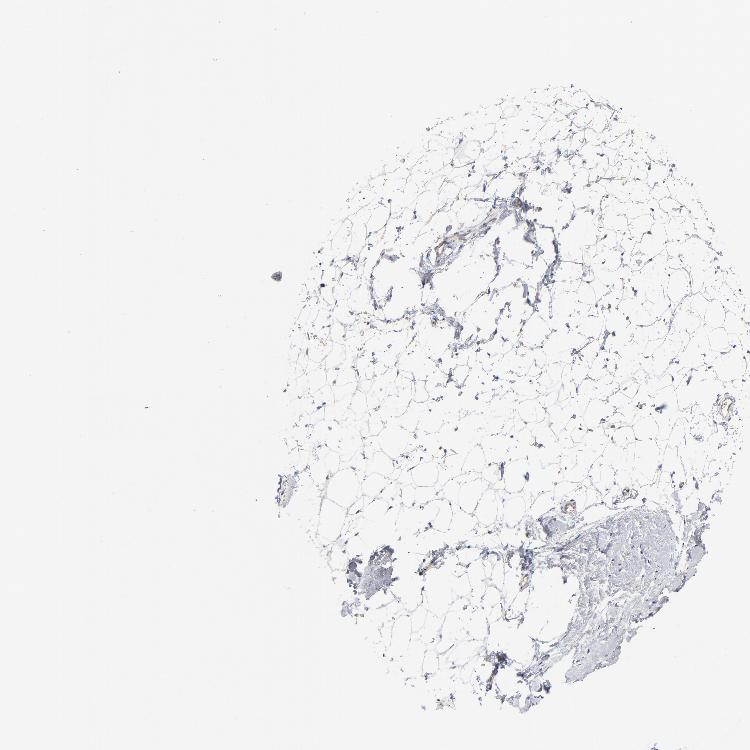

BREAST - Antibody stainingi

Antibody staining in the annotated cell types in the current human tissue is reported as not detected, low, medium, or high, based on conventional immunohistochemistry profiling in selected tissues. This score is based on the combination of the staining intensity and fraction of stained cells.

Each image is clickable and will lead to virtual microscopy that enables deeper exploration of all samples and also displays staining intensity scores, fraction scores and subcellular localization as well as patient and tissue information for each sample.

Antibody HPA003647

Adipocytes Not detected